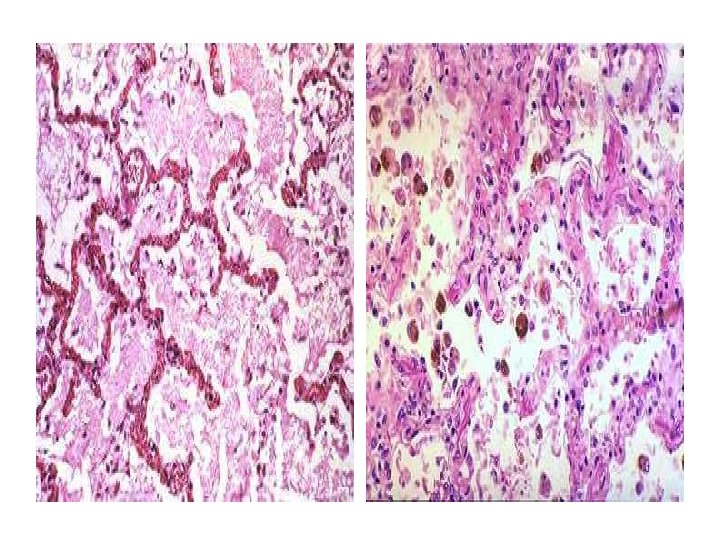

• The lumen of the coronary artery is completely occluded by a dark red thrombus. • What are the most common and the most important cause of arterial thrombosis ?

• What are the components of thrombus? Fibrin, platelets, and red cells. • What are the various fates of thrombi? Propagation, embolism, dissolution, and organization with recanalization.

Which of these fates is clinically most significant in the arterial circulation vs. the venous circulation? • The most significant problem with arterial thrombi is propagation leading to luminal obstruction, resulting in infarction of the tissue supplied. Important examples include myocardial and cerebral infarction. • In contrast, the most significant problem with venous thrombi is the possibility of potentially fatal embolization into the pulmonary circulation